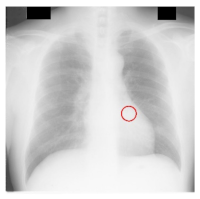

| Filename | Image | JSRT Metadata Notes | Radiologist Observations |

|---|---|---|---|

| JPCLN151.png | ![]() | Extremely subtle 14 mm |

Extremely subtle Behind cardiac silhouette Overlaps vascular marking |

| JPCLN003.png | ![]() | Obvious 30 mm |

Obvious Overlaps vascular markings |

| JPCLN130.png | ![]() | Extremely subtle 30 mm |

Extremely subtle Behind cardiac silhouette |

| JPCLN141.png | ![]() | Extremely subtle 10 mm |

Extremely subtle Behind rib/clavicle |

| JPCLN142.png | ![]() | Extremely subtle 10 mm | Not visible. |